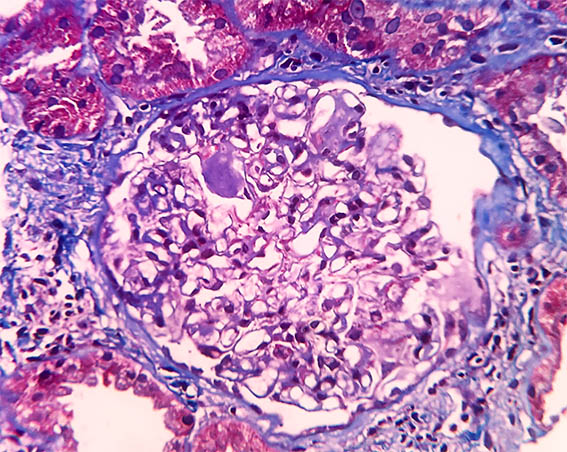

Figure 5. Masson's trichrome stain, X400.